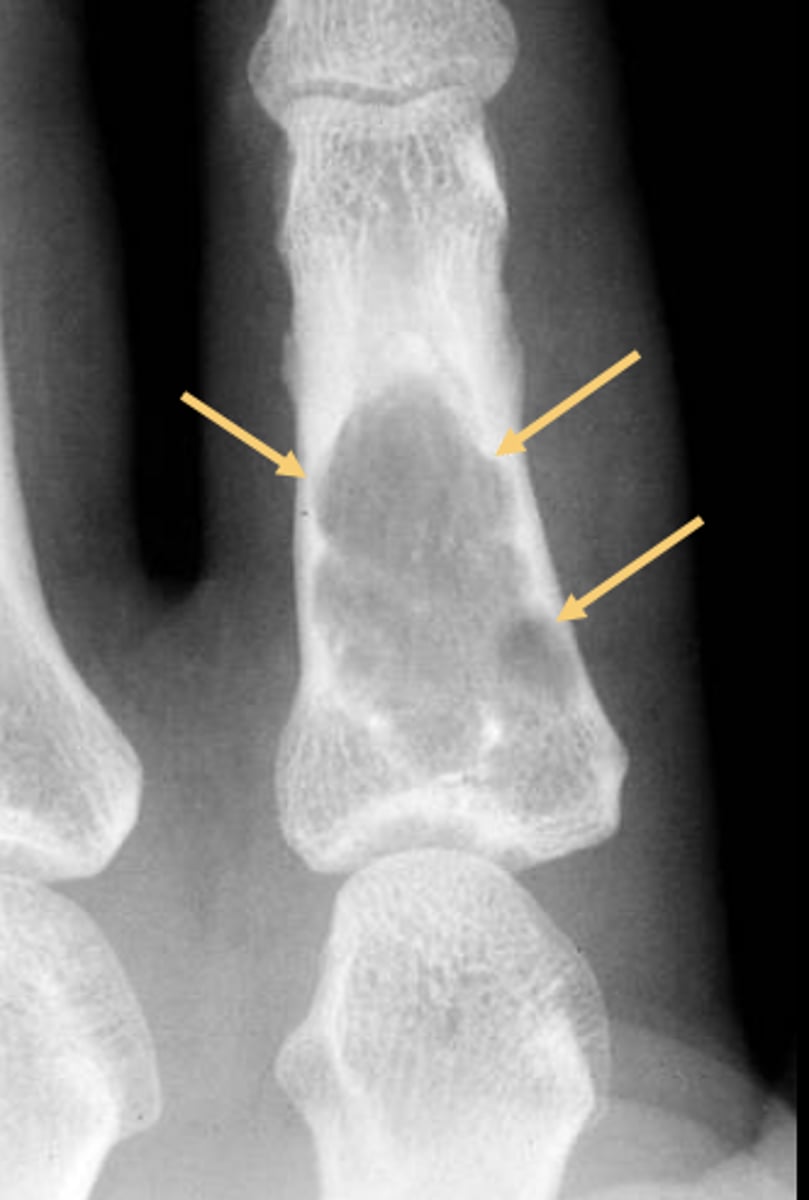

Geographic bone blister

ID radiographic feature of non-ossifying fibroma indicated by top arrow

Septations

ID radiographic feature of non-ossifying fibroma indicated by bottom arrow